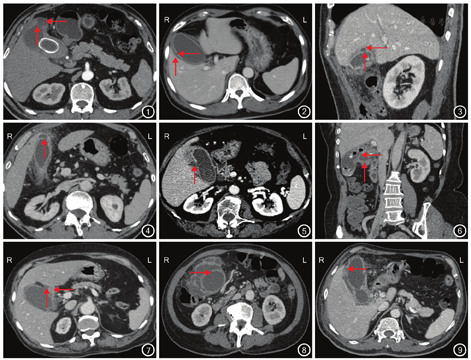

(2)亚急性胆囊穿孔破口情况。①部位和数目:胆囊底部11例(图1),体部7例(图2,图3;1例为体部多处穿孔),颈部1例,底部和体部多处穿孔2例,3例因胆囊与周围脓肿融合,形态改变,无法判断穿孔部位;②最大径:2例隐匿性破口最大径<0.2 cm(图4),其余22例患者破口最大径为0.5 cm(0.2~1.0 cm)。

(3)"堰塞湖征"影像学表现:24例患者均有"堰塞湖征",表现如"1.5"中"堰塞湖征"定义所述(图5,图6)。①环形壁构成:环形壁为脓肿壁(图1,图3)、肝脏边缘(图2)、两者共同构成(图7)分别为15、3、6例;②胆囊被脓肿包绕:局部和完全包绕分别为21例和3例,前者胆囊形态未完全改变,后者胆囊成为脓肿的一部分,胆囊形态不能显示,病灶与周围肠管、肝脏不能清楚分界(图8)。

(4)胆囊情况。①形态:24例患者中,胆囊体积明显增大和轻度缩小分别为23例和1例,胆囊壁塌陷或膨出,1例胆囊腔内见点状积气影;②最大直径:中位值10.0 cm(6.0~13.0 cm);③胆囊壁厚度:中位值0.5 cm(0.3~1.3 cm),水肿增厚,3例胆囊壁分层,3例胆囊壁见多发小溃疡(图9)。

(5)其他积液征象:24例患者胆囊周围脂肪间隙密度增高,部分呈线条状、索条状改变。除"堰塞湖征"积液外,1例患者肝包膜下见少量固定弧形积液影,1例腹膜内见少量固定条形积液影,4例胆囊与肝脏间见积液影,密度明显高于胆汁,6例见肝脓肿形成。